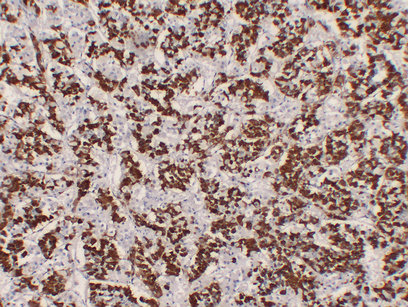

Immunohistochemistry analysis of paraffin-embedded Pituitary using Growth Hormone antibody.High-pressure and temperature Sodium Citrate pH 6.0 was used for antigen retrieval.